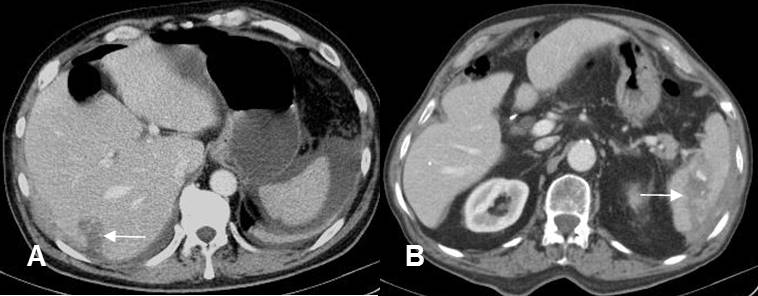

Fig 147. Lesión de vísceras.

A y B: TAC Axial. Imágenes hipodensas y lineales en el hígado y el bazo, que corresponden a contusiones. Se encuentra líquido periesplénico en ambos casos.